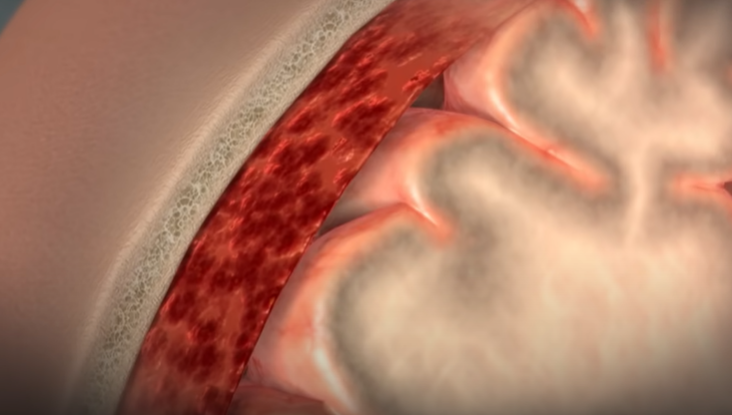

뇌혈관은 총 3겹의 층으로 이뤄져 있는데, 안쪽에 있는 혈관 벽이 찢어지면,

피가 그 사이로 흘러 마치 뇌동맥류처럼 부풀어 오른다.

동맥을 단단히 감싸고 있는 층이 찢어지면 동맥을 감싸는 힘이 없어지기 때문에 동맥의 일부가 밖으로 튀어나오게 된다. 그러면서 동맥류의 형태로 불룩하게 꽈리처럼 생기는 것을 해리성 뇌동맥류라 한다. 기본적으로 동맥 박리가 먼저 일어나고, 동맥의 모양이 쭈글쭈글해진다든지 내피세포가 손상되어 동맥이 막혀 뇌경색이 생기거나 또는 동맥의 해리(떨어져 나감)가 밖으로 진행돼서 동맥을 싸고 있는 외피가 찢어지면 밖으로 출혈이 생긴다.